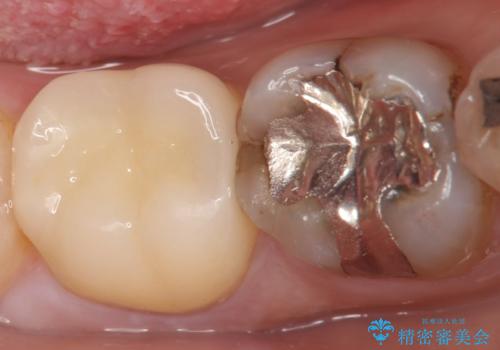

古い樹脂やカリエスを除去後、形を整え、オールセラミッククラウンによる補綴を行いました。

今回用いたオールセラミッククラウンはジルコニアフレームという白い素材の上にセラミックを盛っているため、審美性が非常に高いのが特徴です。

また、ジルコニアは人工ダイヤモンドの材料にも使われているほど高い強度を持っており、そのためオールセラミッククラウンは審美性だけでなく、奥歯やブリッジの補綴も可能とするクラウンです。